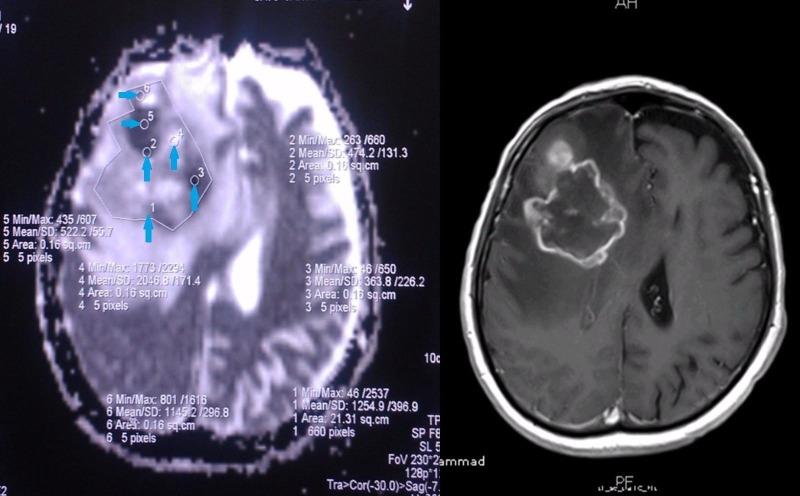

Introduction The apparent diffusion coefficient (ADC) sequence is based on the diffusion properties of water molecules within tissues and correlates with tissue cellularity. ADC may have a role in predicting tumor grade for gliomas, and may in turn assist in identifying tumor biopsy sites. The purpose of this investigation was to assess the competence of preoperative ADC values in predicting tumor grades. Methods This was a retrospective investigation. We calculated the ADC values in the areas of greatest restriction in solid tumor components, and we recorded the pattern of contrast enhancement. Pathology reports masked to the imaging results were reviewed independently. We calculated the differences in the mean values of different tumor grades and high-grade and low-grade gliomas. A receiver operator curve (ROC) analysis assessed the predictive potential of ADC values for low-grade gliomas. Results Forty-eight cases of glioma were included in our study. We noted a statistically significant difference in the lowest mean ADC values for the tumor regions of Grade IV lesions (333.83 ± 295.47) compared with Grade I lesions (653.20 ± 145.07). On ROC analysis, we noted an area under the curve (AUC) of 0.80 for the lowest ADC value in the whole tumor region, which was a predictor of low-grade glioma with 95 % confidence interval (CI) of 0.675-0.926. The sensitivity of the lowest ADC value was 84.5% for high-grade lesions. Conclusion Given our findings that the means of the lowest ADC value are significantly different between low and high-grade gliomas with an AUC of 0.80 for ADC as a predictor of low-grade lesions and a sensitivity of 84.5% for high-grade lesions, ADC values contain some predictive properties of tumor grading. ADC values may be a valuable parameter in the assessment and treatment of tumors.

引言 表观扩散系数(ADC)序列基于水分子在组织内的扩散特性,并与组织细胞密度相关。ADC在预测神经胶质瘤的肿瘤分级方面可能具有一定作用,进而有助于确定肿瘤活检部位。本研究的目的是评估术前ADC值预测肿瘤分级的能力。

方法 这是一项回顾性研究。我们计算了实体瘤成分中限制最明显区域的ADC值,并记录了对比增强模式。对与影像结果无关的病理报告进行独立审查。我们计算了不同肿瘤分级以及高级别和低级别神经胶质瘤的平均值差异。采用受试者工作特征曲线(ROC)分析评估ADC值对低级别神经胶质瘤的预测潜力。

结果 我们的研究纳入了48例神经胶质瘤病例。我们注意到,IV级病变肿瘤区域的最低平均ADC值(333.83±295.47)与I级病变(653.20±145.07)相比,存在统计学上的显著差异。在ROC分析中,我们发现整个肿瘤区域最低ADC值的曲线下面积(AUC)为0.80,这是低级别神经胶质瘤的一个预测指标,95%置信区间(CI)为0.675 - 0.926。最低ADC值对高级别病变的敏感性为84.5%。

结论 鉴于我们的研究结果表明,低级别和高级别神经胶质瘤之间最低ADC值的平均值存在显著差异,ADC作为低级别病变预测指标的AUC为0.80,对高级别病变的敏感性为84.5%,ADC值具有一些肿瘤分级的预测特性。ADC值可能是肿瘤评估和治疗中的一个有价值的参数。